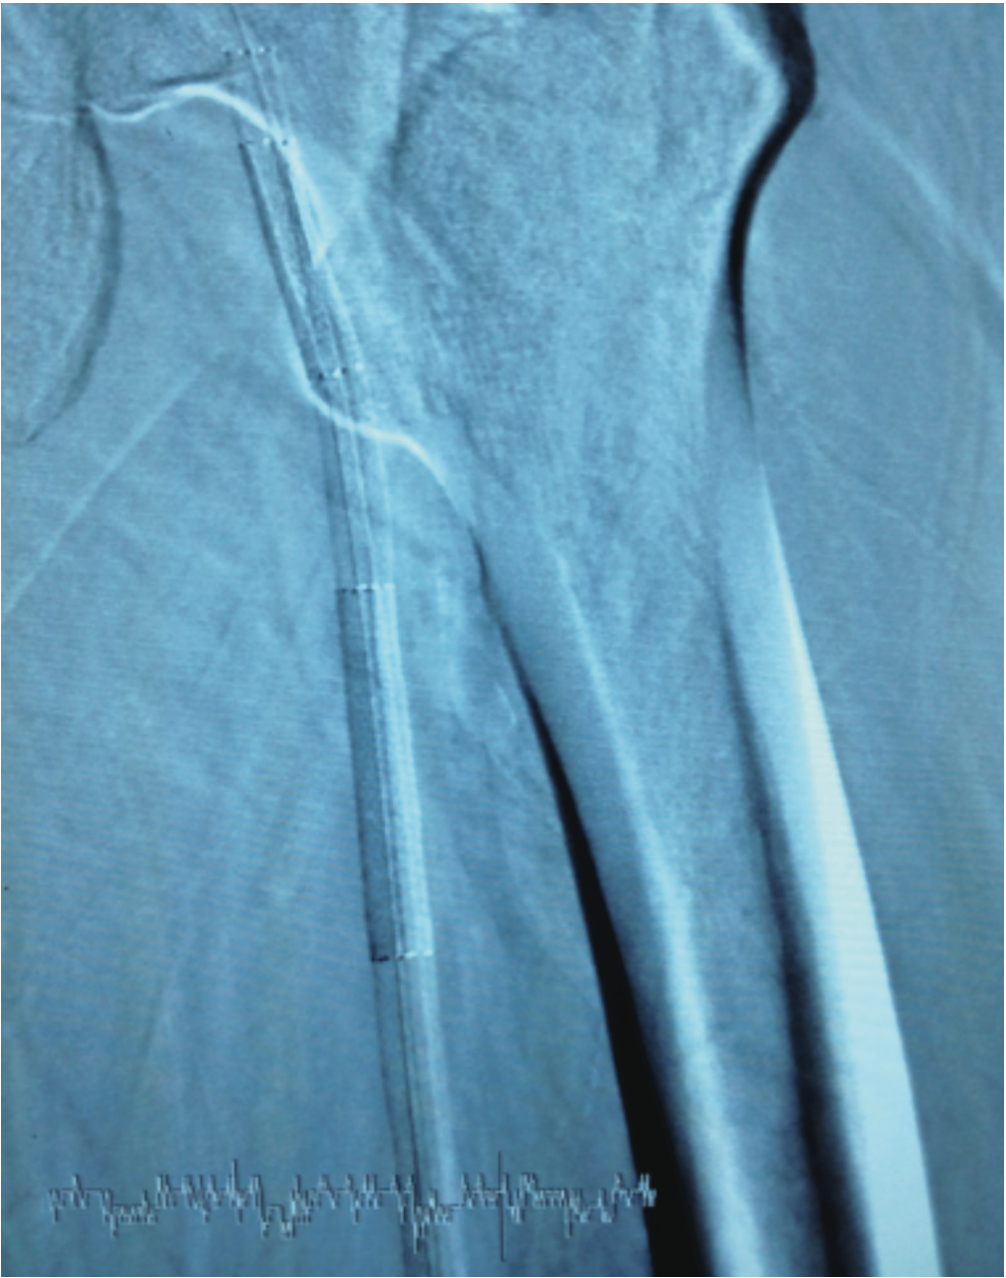

While maintaining the Runthrough NS wire in position, we advanced a 0.014-inch x 300 cm Spartacore guide wire (Abbott Vascular) from the right CFA with a Quick-Cross support catheter. We carefully navigated the wire through the entire length of the SFA into the left popliteal artery and distally into the left anterior tibial artery. At this point, we deployed four self-expanding 6 mm FlexStents (Cordis) in an overlapping fashion, measuring 380 mm in length, extending from the left distal SFA all the way up to the left SFA ostium at the level of the CFA (Figure 6). We performed final balloon angioplasty to expand the stent struts with a 5 mm x 220 mm Savvy balloon (Cordis). Final angiography showed excellent results with good distal flow (Figure 7).